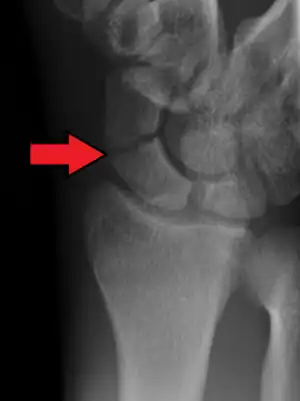

| X-ray showing a scaphoid fracture, the most common wrist fracture | |

Carpal fractures are fractures that involve the bones of the wrist. Symptoms may be none specific.[1] Fractures of the scaphoid are most common, while the others are rare.[1]

The underlying cause is typically a fall onto an outstretched hand (FOOSH).[1] X rays of the wrist may be unclear, and CT scan may be required.[1]